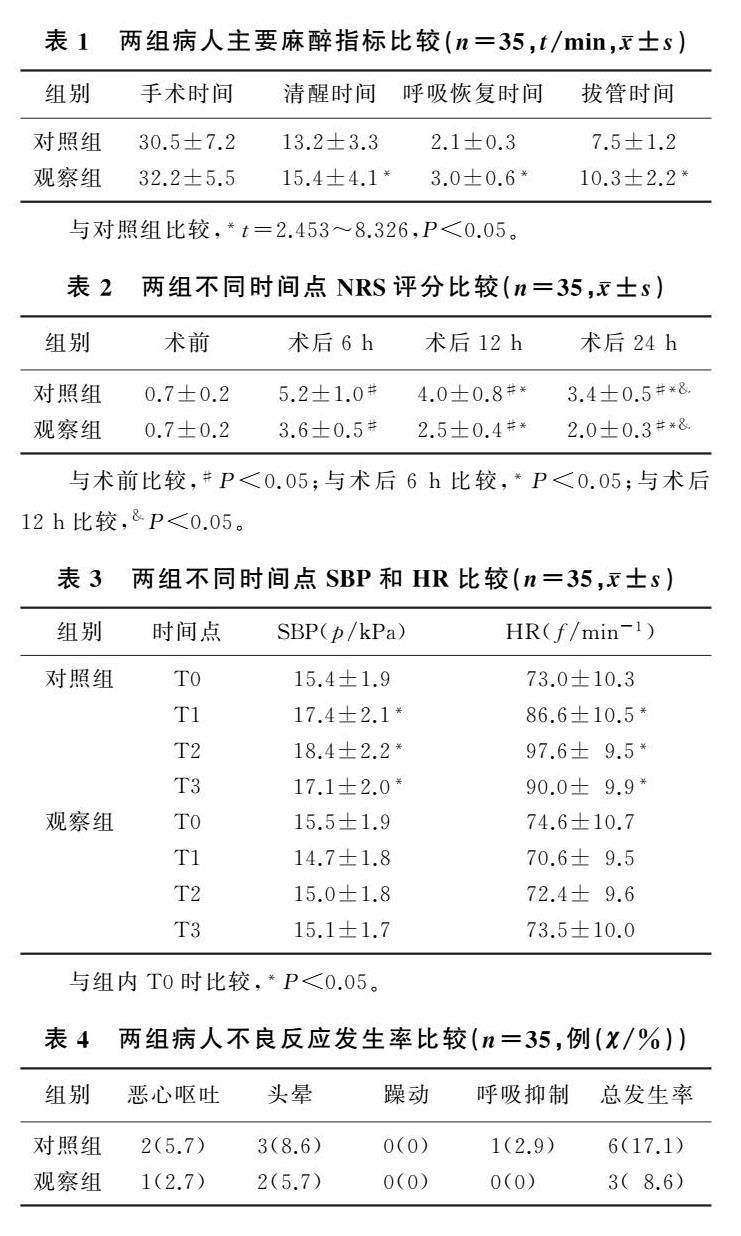

论著 | SAPB复合RSB对肝癌切除术病人苏醒及镇痛影响

论著 | SAPB复合RSB对肝癌切除术病人苏醒及镇痛影响

论著 | 艾司氯胺酮与舒芬太尼对肝硬化并发肝癌病人微波消融术麻醉效果比较

论著 | 艾司氯胺酮与舒芬太尼对肝硬化并发肝癌病人微波消融术麻醉效果比较